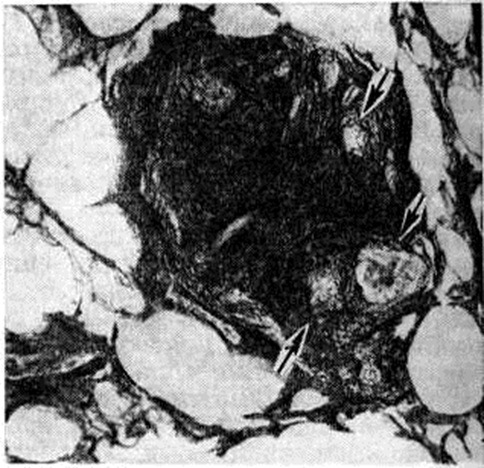

Рис. 3.

Микропрепарат лёгкого с организующейся туберкулёзной гранулемой: в центре поля зрения видна организующаяся туберкулёзная гранулема, пронизанная густой сетью аргирофильных волокон, отсутствующих лишь в участках, где расположены гигантские клетки Пирогова — Лангханса (указаны стрелками); импрегнация серебром; ×280.